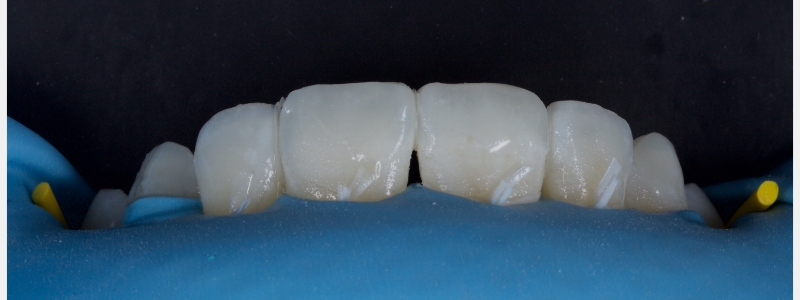

The worn incisal edges were restored with edge bonding, a new technique for restoring worn dentition. This should be regarded as a multiple Class IV restoration.

Usually, the composite resin is layered using a polyvinyl siloxane (PVS) palatal stent. Layering allows accurate control from palatal to facial, reducing the need for significant post-op occlusal adjustment.